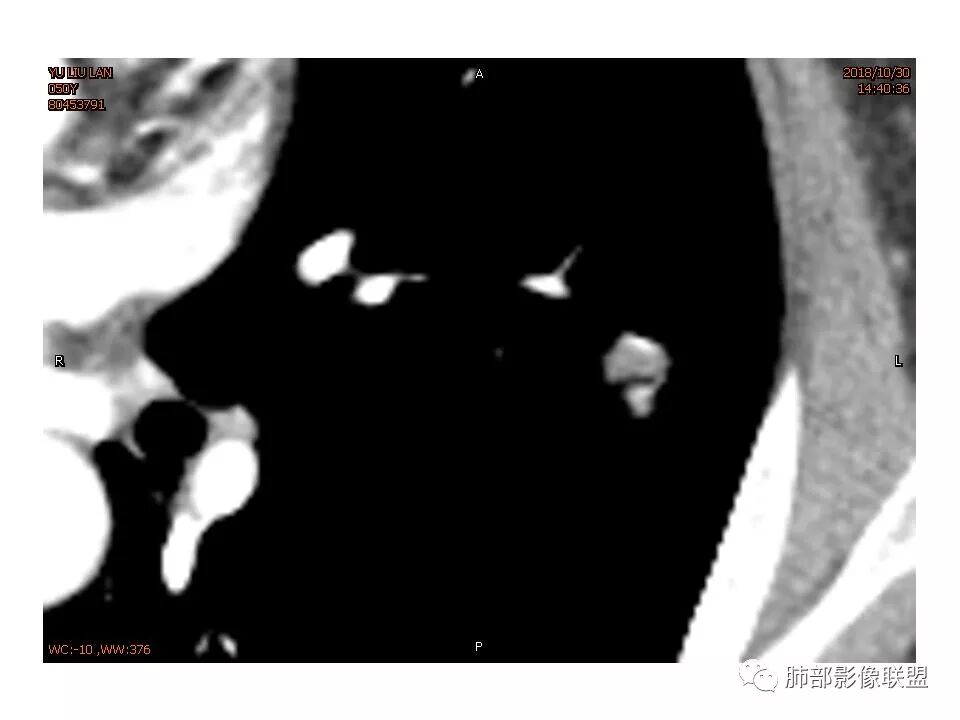

女,50。实性不规则结节,大小12*13mm,分叶、毛刺、胸膜凹陷,牵拉力强,增强渐进性强化,动脉期强化20,静脉期还有进一步强化。边缘强化,点状坏死。

其内血管被破坏。

女性,50岁。U型凹陷、平直征

南边:支持炎性

这些层面不大放心

南边 :

我倾向于炎性结节,癌待排